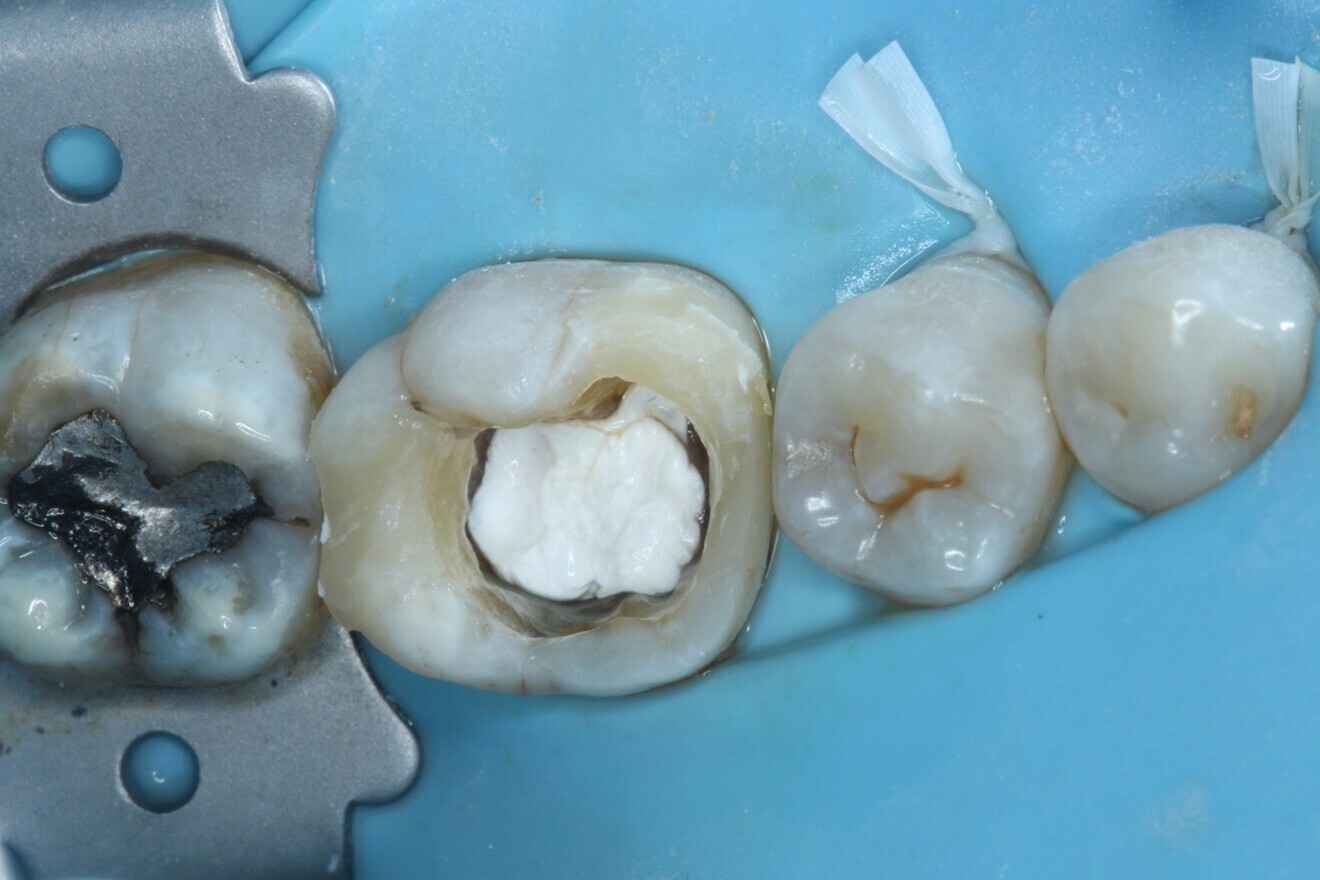

Fig. 2: Dental dam isolation.

Local anaesthesia was administered with 4.4 ml of 2% lidocaine hydrochloride with 1:80,000 adrenaline via buccal infiltration and inferior dental nerve block. A dental dam was placed over teeth #37–34 using a HYGENIC Fiesta #7 clamp (COLTENE) and double floss ties to provide a tight seal (Fig. 2). The tooth was reassessed with caries removal having been carried out (Fig. 3), and four orifices located. The mesial cavity margin was deemed restorable; however, deep marginal elevation would be required. A decision was made to carry out the deep marginal elevation after cleaning and shaping of the root canal system to improve or maintain access to the root canal system.